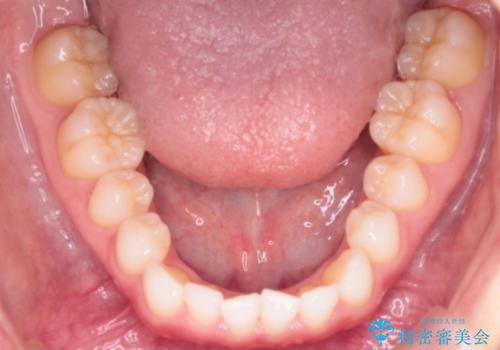

下顎骨が右側に偏位していることにより下顎前歯の真ん中はずれています。